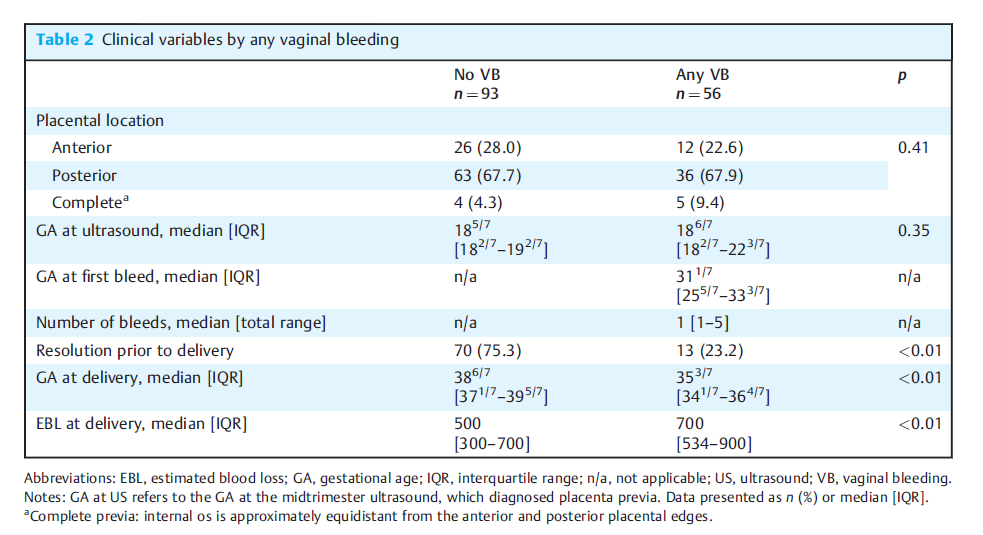

结果:149例前置胎盘患者中,超声时的中位胎龄为18+6周(IQR, 18+2-19+2)。37%发生VB,15%发生需要分娩的VB。VB患者首次出血的中位胎龄为31+1周(IQR, 25+3-33+3),需要分娩的VB患者的中位胎龄为32周(IQR, 27-34+1)。83例(55.7%)患者在中位胎龄28+3周(IQR, 25-31+6)时通过随访超声发现前置胎盘。未经历过VB的女性中,有75.3%(0.70)的人有缓解,而经历过VB的女性中,只有23.2%(0.13)的人有缓解。除了有过>1次剖宫产的比率在有过VB的妇女中更高。需要分娩的VB妇女比不需要分娩的妇女有更多的VB发作(1.5,四分位数范围[IQR][1 - 3]对1.0 [1 - 5];P < 0.001)。与有VB的妇女相比,没有VB的妇女分娩明显延迟(38+6周vs. 35+3周;p < 0.01),分娩时的中位EBL和估计失血量(EBL)显著低于500[300-700]和700 mL [534 - 900];p < 0.01),见下表。